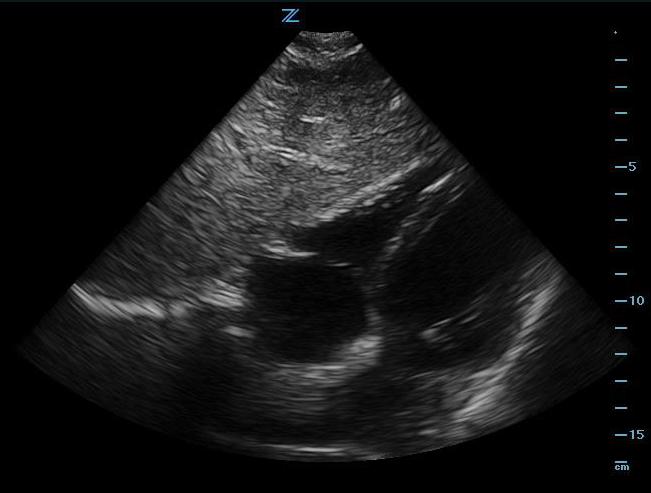

Subxiphoid Four-Chamber View

- Place the probe in the subxiphoid region with the transducer indicator toward the patients’ right side or right shoulder. Angle the probe toward the left shoulder.

- This view shows the right ventricle immediately adjacent to the left lobe of the liver. (Figure 2, Video 1) A pericardial effusion will be easily recognized between the liver and the heart. (Video 2)

- Increasing the depth of the image, applying more pressure, and having the patient take a deep breath will improve chances of obtaining a good image.

- Illustration 2. Cardiac anatomy from subxiphoid view

- Figure 2. Subxiphoid view